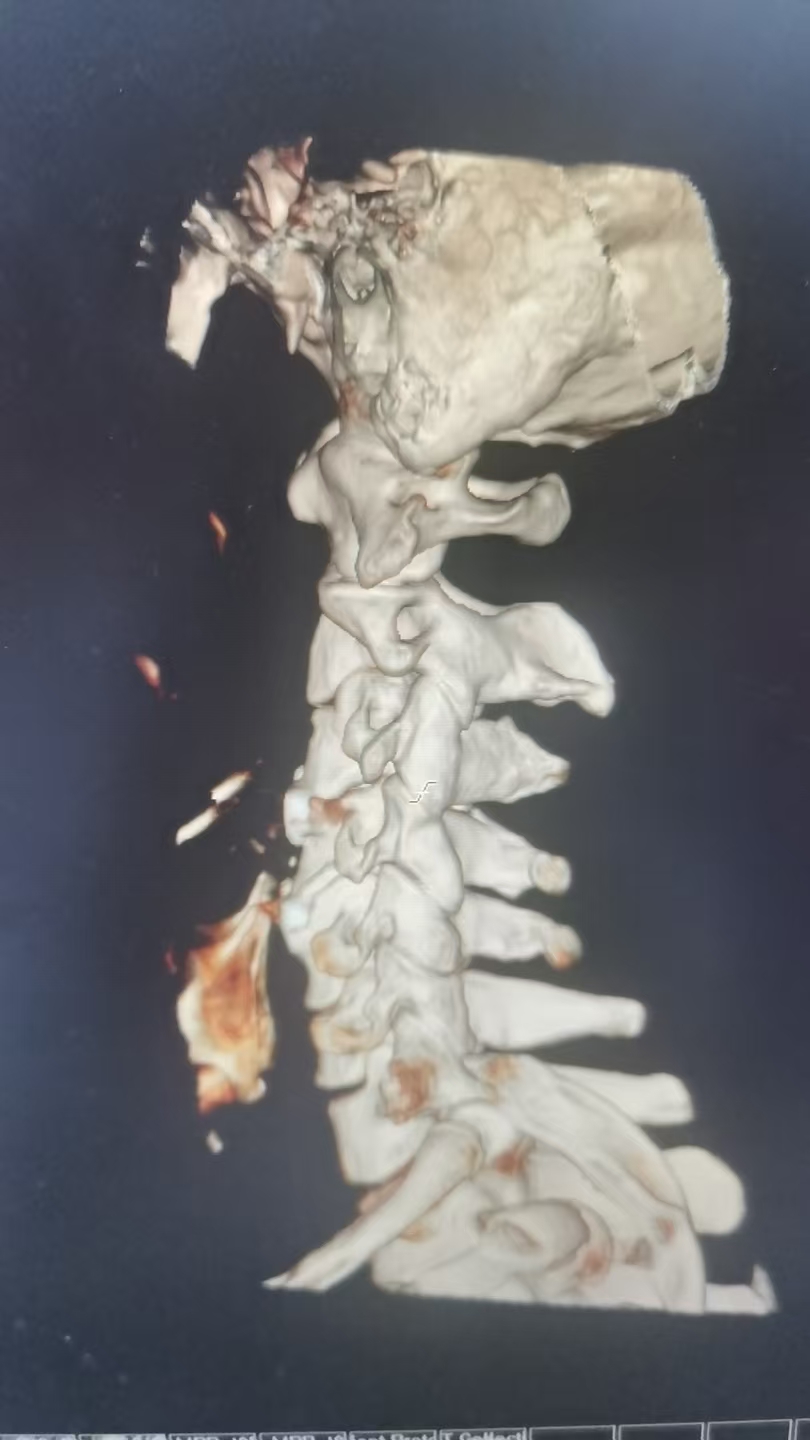

47岁李先生(化名)近日因车祸导致“颈髓损伤,四肢麻木无力”入院。经我院脊柱外科团队详细检查,影像学检查显示颈3/4及4/5节段椎间盘突出,脊髓神经根受压,引发四肢不完全瘫痪。术前右侧上、下肢体肌力:3级,左上肢肌力3级,左下肢肌力1级。

由于保守治疗效果不明显,医护团队综合评估后,决定为患者施行颈椎前路微创手术。在南医三院派驻骨科专家、东凤人民医院副院长闫慧博(挂职)的带领下,我院骨科团队共同为患者实施“颈椎3/4、4/5双节段前路椎间盘摘除+椎体融合术”。

(术后图)